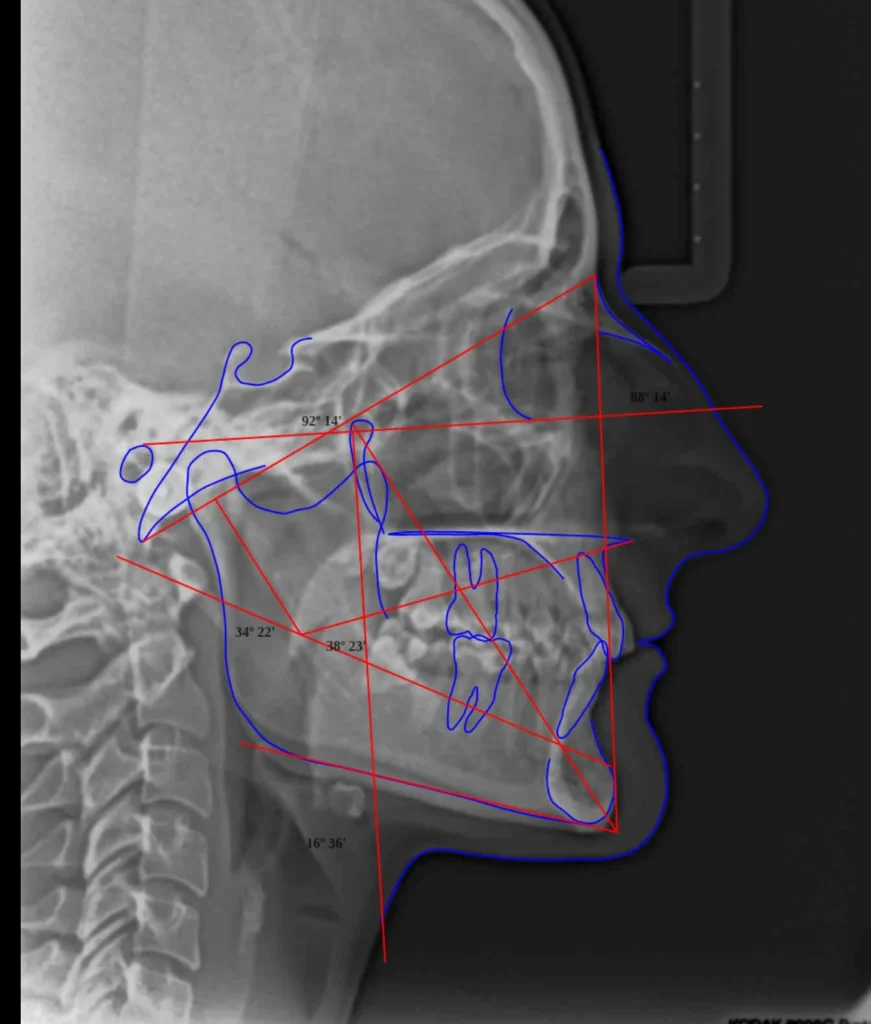

Estudios cefalometricos

En Ident3D, nos enorgullece ofrecer un conjunto completo de cefalogramas de última generación,